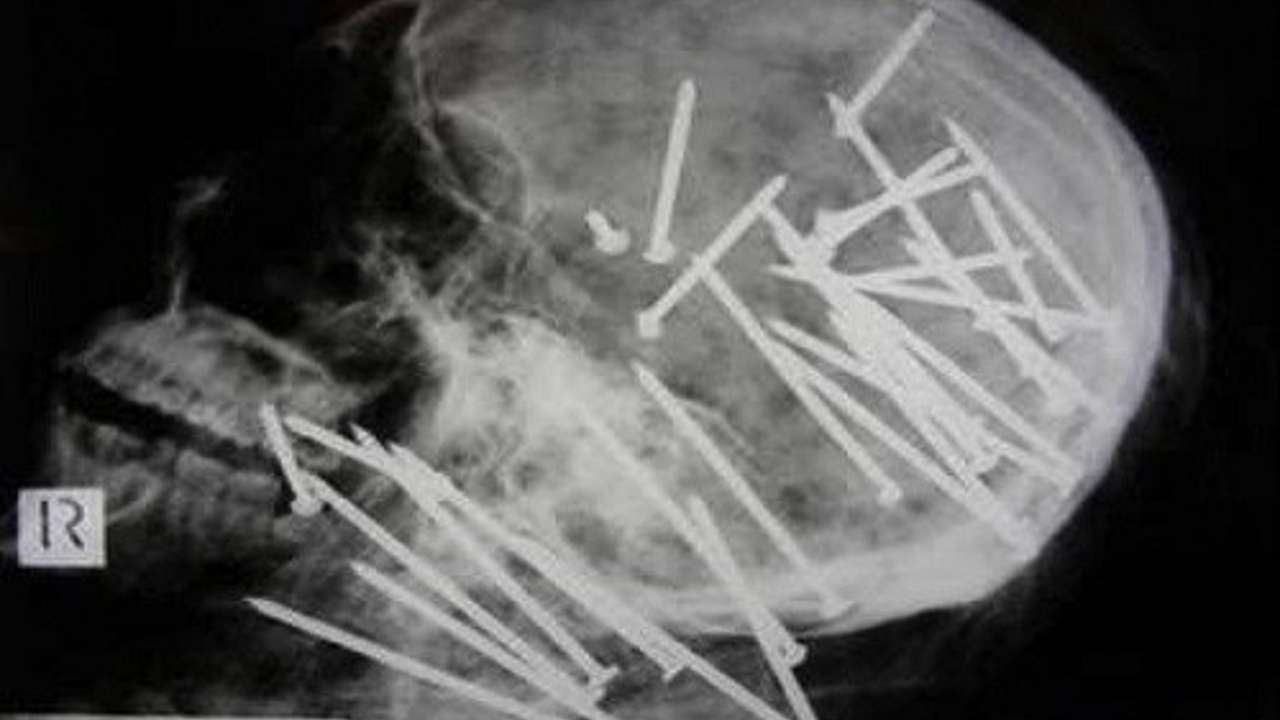

5-) 27 yaşındaki Çinli bir adamın öldükten sonra çekilen röntgeni doktorları çok şaşırttı. Çinli adamın çivi tabancasıyla öldürüldüğü ortaya çıktı.

4 7